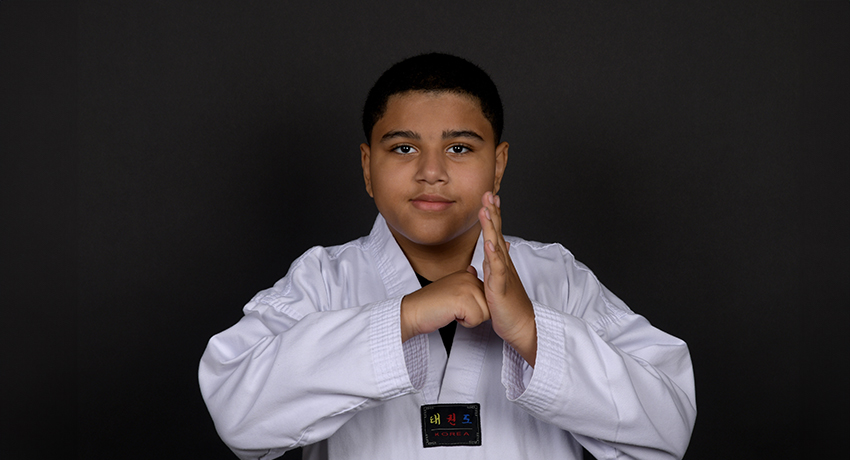

“Every time I look in the mirror, it makes me want to smile so hard, knowing that my back is straight. It makes me happy,” said Louis Florentino, 11, regarding his scoliosis surgery.

“It was something I had to overcome, and I overcame it. I’m super glad I did it,” Louis said.

Louis is ahead of the curve after his first post-op appointment. His body has hit milestones that usually take kids months to achieve, such as balancing out his shoulders. The body has to get used to its new position in space, and his has already adjusted. Sitting on the floor for Taekwondo without pain will be a meaningful outcome once he’s completely recovered to return to his favorite activity.

“I feel very confident now,” Louis said. “The most important part is seeing my parents happy now that my back is straight.”